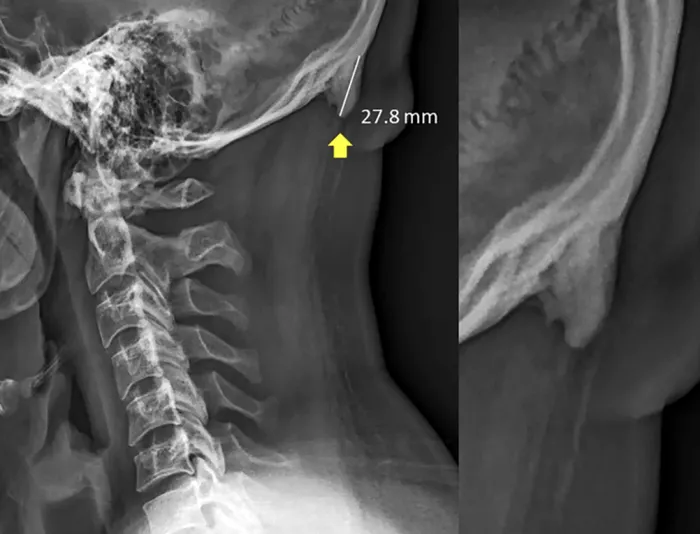

Majoritatea „coarnelor” apărute în partea din spate depășesc 10 milimetri, spun cercetătorii, iar unele pot ajunge chiar la aproape 28 de milimetri.

Nu te grăbi să te sperii că te vei trezi cu coarne în frunte din cauza telefoanelor. Nu e vorba de așa ceva. Apar, de fapt, niște modificări în partea din spate a capului, niște proeminențe osoase, cauzate de înclinarea în fața a capului, adică exact ce faci atunci când stai cu ochii în telefon non-stop.

Autorii studiului susțin că acest lucru se întâmplă din cauza presiunii asupra mușchilor. Din cauza poziției, pot fi resimțite și anumite dureri. De exemplu, pot apărea dureri de cap şi dureri în partea superioară a spatelui şi în zona cefei.